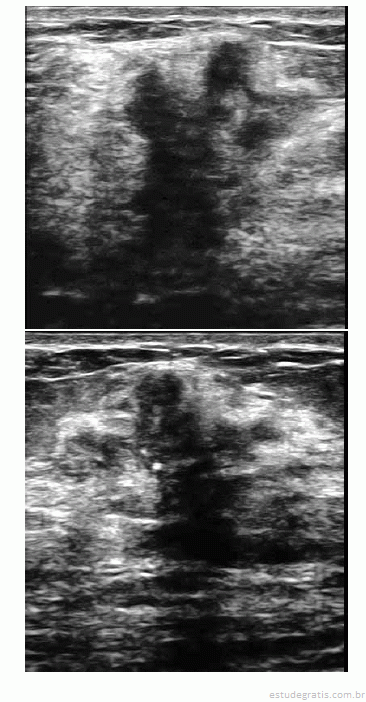

Uma paciente de 32 anos de idade procurou um médico ginecologista por ter palpado nódulo na mama direita. Ao exame das mamas, foi percebido nódulo endurecido, fixo aos planos adjacentes, com cerca de 3 cm de diâmetro. Foi realizada, então, mamografia, que revelou presença de lesão espiculada, com limites imprecisos, retração do parênquima adjacente e microcalcificações pleomórficas agrupadas. O exame ultrassonográfico evidenciou a lesão representada na forma gráfica na figura abaixo.

A respeito dessa situação hipotética, julgue os itens de 75 a 80.

Microcalcificações são os achados ecográficos que mais elevam o risco de malignidade, quando encontradas em nódulos mamários suspeitos.